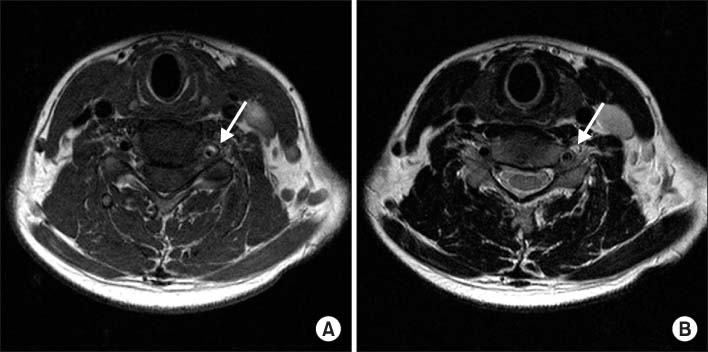

Fig. 4

(A) T1 weighted and (B) T2 weighted cervical spine MRI images of patient 2. In T1 weighted image, signal voiding of right vertebral artery (arrow) is narrower than that of left vertebral artery. Thickening with high signal intensity (arrow) is also noted on T2 weighted image.

Fig. 4 (A) T1 weighted and (B) T2 weighted cervical spine MRI images of patient 2. In T1 weighted image, signal voiding of right vertebral artery (arrow) is narrower than that of left vertebral artery. Thickening with high signal intensity (arrow) is also noted on T2 weighted image.